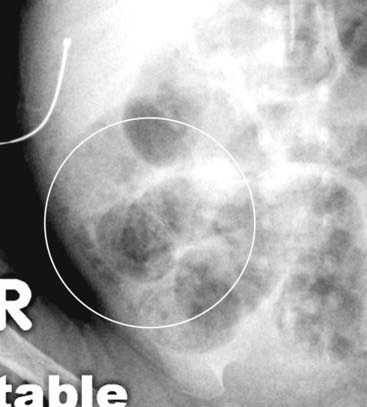

Figure 15-12 Pneumatosis seen en face.

Close-up of the right lower quadrant in another infant shows multiple faint, mottled lucencies in the right lower quadrant (white circle), which is the appearance of pneumatosis intestinalis when seen en face. The density has the same appearance as air mixed with stool, but can be distinguished from stool because it occurs in areas stool might not be expected and it does not change over time. This infant also had necrotizing enterocolitis.